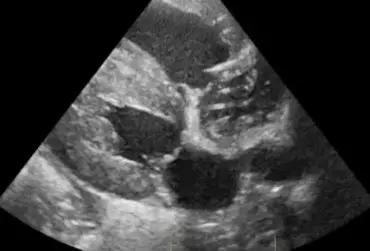

Torbiel pierwotna jest rzadką wadą rozwojową występującą u człowieka, psa, kota i konia. W niniejszym artykule opisano przypadek torbieli pierwotnej jelita prostego u dziewięcioletniego kota rasy Manx, u którego występowały przewlekłe zatwardzenia. W badaniu rektalnym i radiograficznie stwierdzono obecność miękkiego guza dogrzbietowo i bocznie od jelita grubego. Badaniem ultrasonograficznym i w tomografii komputerowej uwidoczniono dobrze odgraniczoną, cienkościenną torbiel, częściowo zamykającą światło kanału miednicy. Torbiel usunięto chirurgicznie z dojścia okołoodbytowego. Nie stwierdzono połączenia torbieli ze ścianą prostnicy. Badanie histopatologiczne potwierdziło postawione podejrzenie torbieli pierwotnej. Po wykonanym zabiegu objawy kliniczne całkowicie ustąpiły.